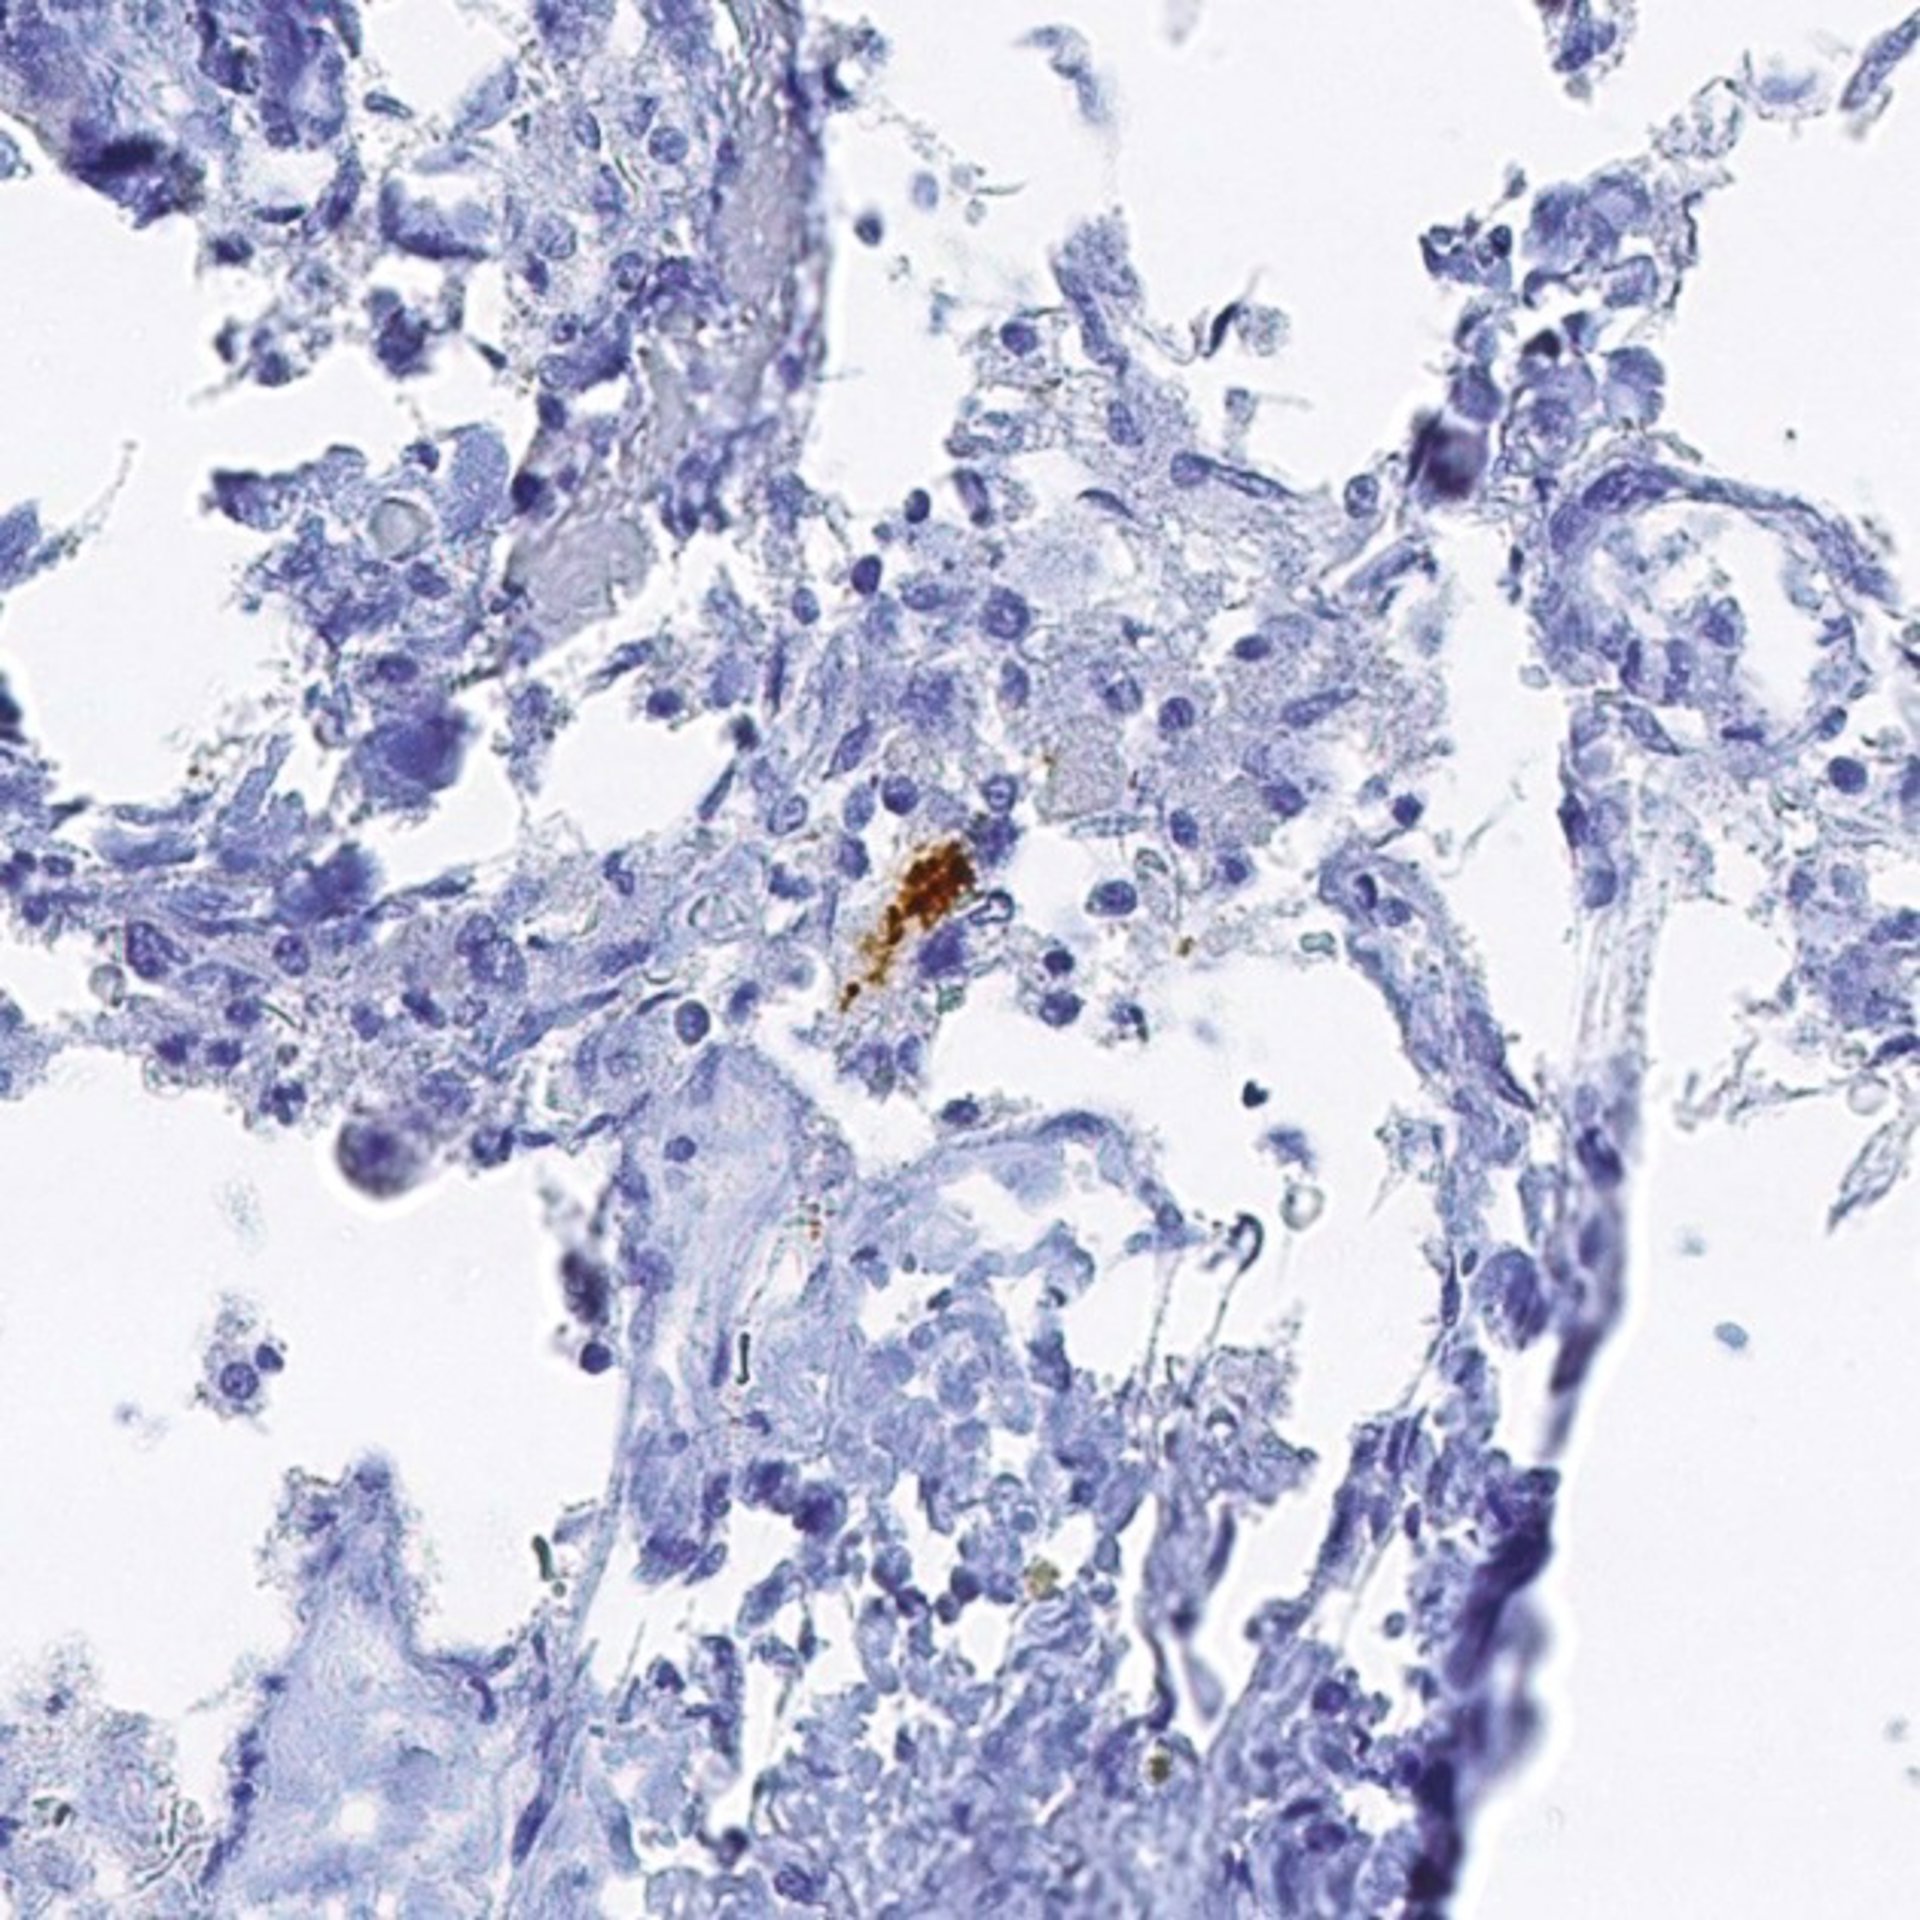

NATURE